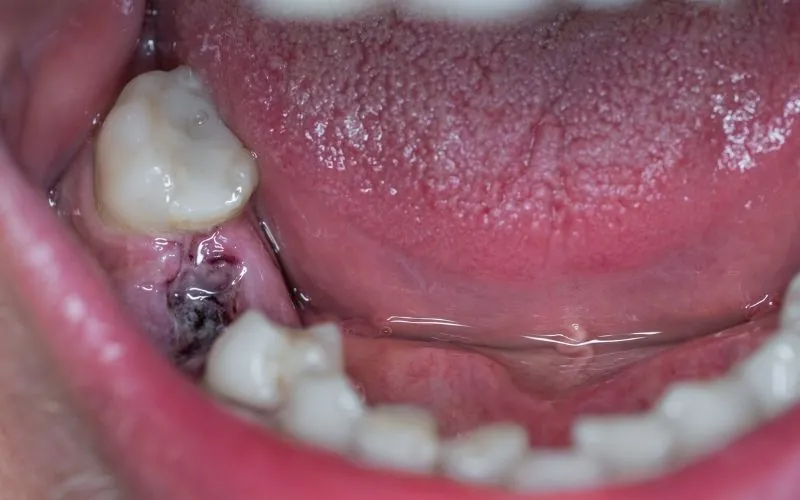

Sundt sår under opheling efter tandudtrækning

Dårlig smag i munden efter fjernelse af visdomstand